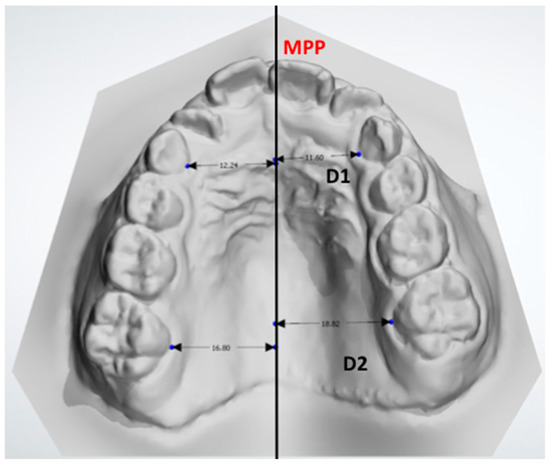

- D1: the distance between the midpoint at the dento-gingival junction of the primary canine from the crossbite and noncrossbite sides compared with the MPP.

- D2: the distance between the midpoint of the dento-gingival junction of the first molar from the crossbite and noncrossbite sides compared with the MPP.